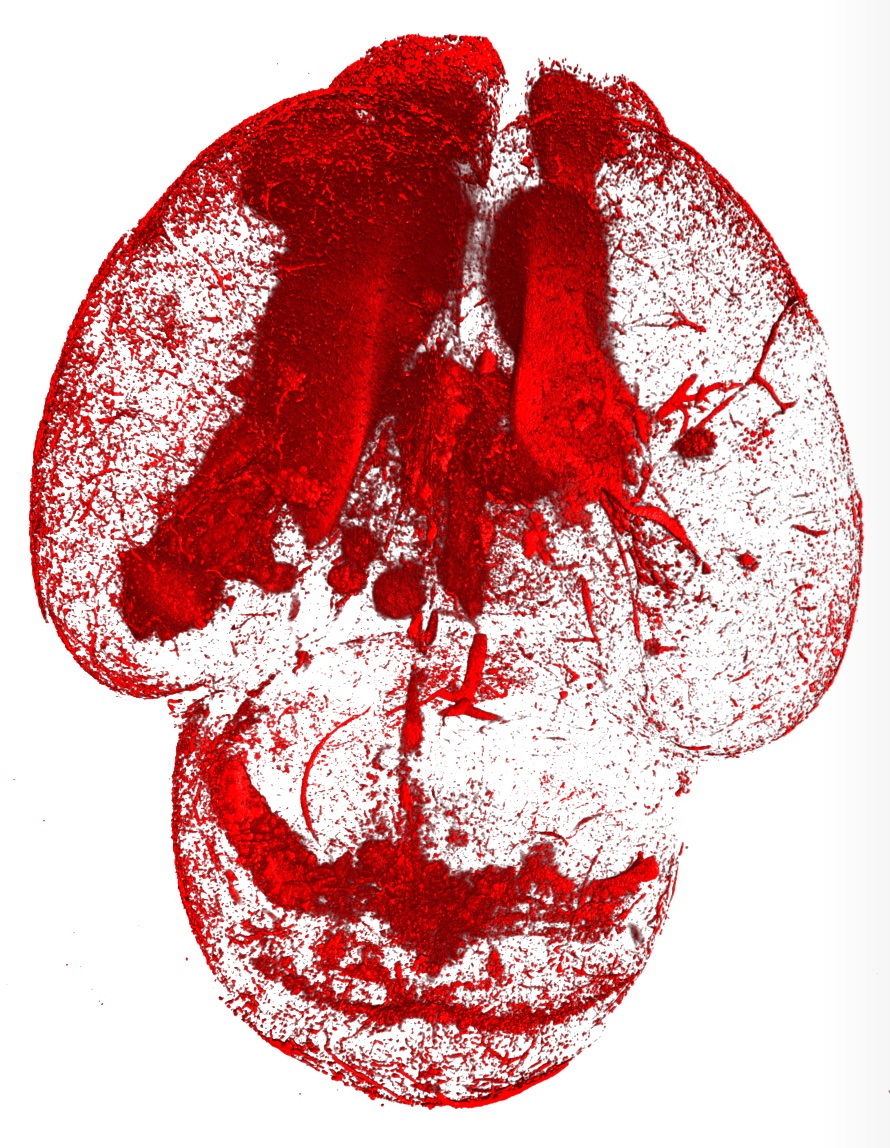

A pre-clinical model showing large areas of the brain with bleeding (blood cells in red)

A new analysis of preclinical models has found brain bleeds always occurred when platelet levels dropped to 10 per cent or below in newborns and foetuses.

By analysing varying degrees of thrombocytopenia in pre-clinical models, researchers were able to distinguish three levels of platelet counts that determined brain bleed risk.

They found brain bleeds in unborn or newborn babies were guaranteed if their platelet count dropped to 10 per cent or below.

While a moderate platelet level between 10-40 per cent could potentially trigger a brain bleed, babies with over 40 per cent of platelets weren’t at risk of developing the condition at all.